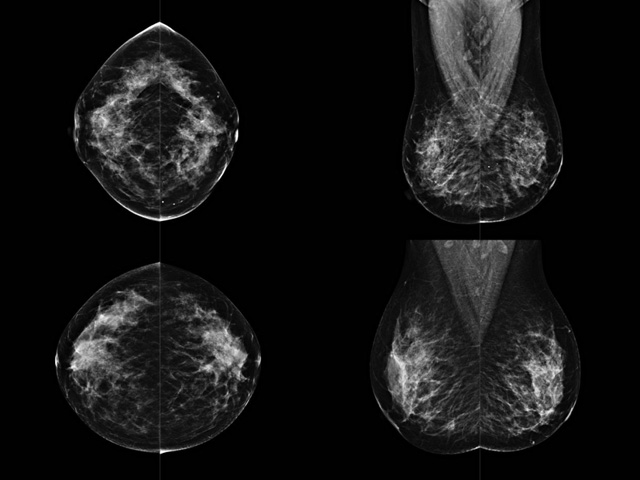

乳腺DR檢查的作用跟有什么細節(jié)需要注意事項

乳房檢查時候要注意一些細節(jié),需要更深入的了解這樣才能使檢查更準確。乳腺DR是乳腺癌的篩查診斷工具設備。是乳房方面檢查的重要影像方法。它可以臨床檢查出早期的乳腺癌。可以判斷良性惡性。因為它可以檢查出早期的病變。對良性惡性檢查的準確率達到90%以上。發(fā)病高峰年齡為45歲到54歲。50歲檢查出來乳腺癌病患,可以讓死亡率下降3成。所以30-40歲女性每年做一次乳腺DR檢查。40歲以上就一年兩次。如果家族史有乳腺癌的30歲以下也需要做檢查。清晰顯示乳腺各層組織嚴重的乳腺增生,乳腺炎,乳腺外傷也建議1年檢查一次。極大提高了早期乳腺癌的敏感度和診斷率。

大角度、高質量的乳腺檢查,可以讓女性帶來身體健康安全。為醫(yī)生提供了高清影像數據。乳腺檢查時候各個部位影像顯示出來。白色乳腺導管跟纖維結締組織。模糊的是脂肪。病變一般是不透明的白色。有需要放大來檢查。乳腺DR沒有重疊偽影。輻射劑量更少。因為乳腺癌發(fā)病每年都有所提高,對女性都造成了嚴重的身體健康危害。早做檢查早治療是不可忽視的舉措。可以大大的降低死亡率。保證身體健康。一般檢查避開經期,來完7天左右是最佳的檢查時間。絕經的女性就沒有要求。孕婦不參加乳腺DR檢查, 6個月內準備妊娠的婦女也不宜行此檢查。